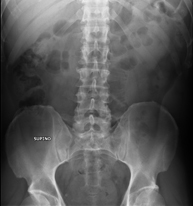

- RX Abdomen

Técnica mediante la cual, utilizando rayos X, se obtienen imágenes del abdomen (estómago, intestino delgado, intestino grueso, hígado, riñones, vejiga, pelvis ósea, etc.) para su estudio. - RX Columna lumbar

Procedimiento que permite, mediante el uso de rayos X, y tras inyectar un contraste en el interior de la articulación, detectar lesiones de determinadas articulaciones (cartílago, hueso, tendones, etc.) según la distribución del contraste. - RX Pelvis

Procedimiento mediante el cual, utilizando rayos X, se obtienen imágenes de la pelvis para su estudio, especialmente de los huesos pélvicos. - RX Edad ósea